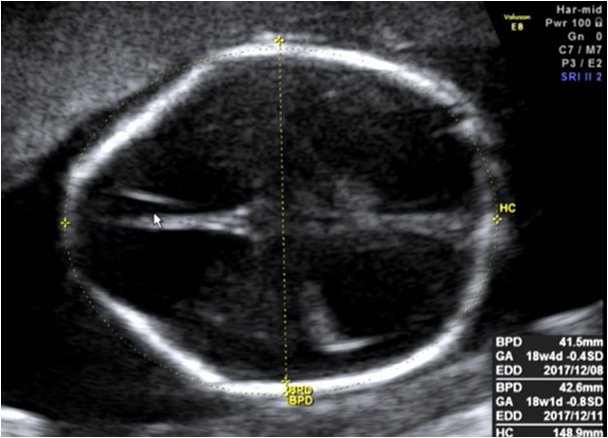

レモンサインは、赤ちゃんの頭の前方がほっそりとして、まるで頭のかたちがレモンに見えることから、その名前がつけられました。

そこで私たちは、お腹の中の赤ちゃんが脊髄髄膜瘤のときに、間接的に見えてくるサインがあるかないかも確かめています。頭の中の脳脊髄液(のうせきずいえき)が増えて、脳室が大きくなる水頭症(すいとうしょう)は分かりやすいサインです。ですが、妊娠の早い時期には脳室がまだ大きくなっていないこともあります。そのため、別に確認すべきサインがあります。

それがレモンサインとバナナサインです。